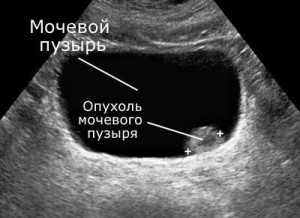

- Ультразвуковое исследование. Звуковые волны способны уточнить размер, тип и структуру образования. Также выясняется, не задеты ли соседние органы;